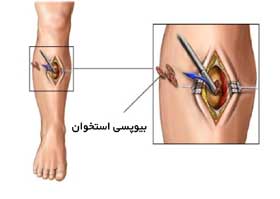

روش های عکس برداری می توانند به تعیین محل و اندازه ی تومورهای استخوان و گسترش یا عدم گسترش آن ها به سایر نقاط بدن کمک کنند. در این مقاله با علائم سرطان مغز استخوان و نیز روش های درمان آن آشنا می شوید. یک تومور رشد غیر طبیعی بافت در بدن است. سلول های توموری توانایی تنظیم کردن ندارند بنابراین سلول های بیشتری تولید می کنند و منجر به تشکیل یک توده می شوند در حالی که بسیاری از تومورها سرطانی.

تشخیص سرطان استخوان. استئوسارکوم شایع ترین نوع است که بیشتر بر کودکان و نوجوانان زیر 20 سال تأثیر می گذارد. جراحی اغلب اولین انتخاب درمانی می باشد اگرچه گاهی اوقات قطع کردن عضو لازم می باشد. درمان سرطان استخوان به نوع سرطان بستگی دارد.